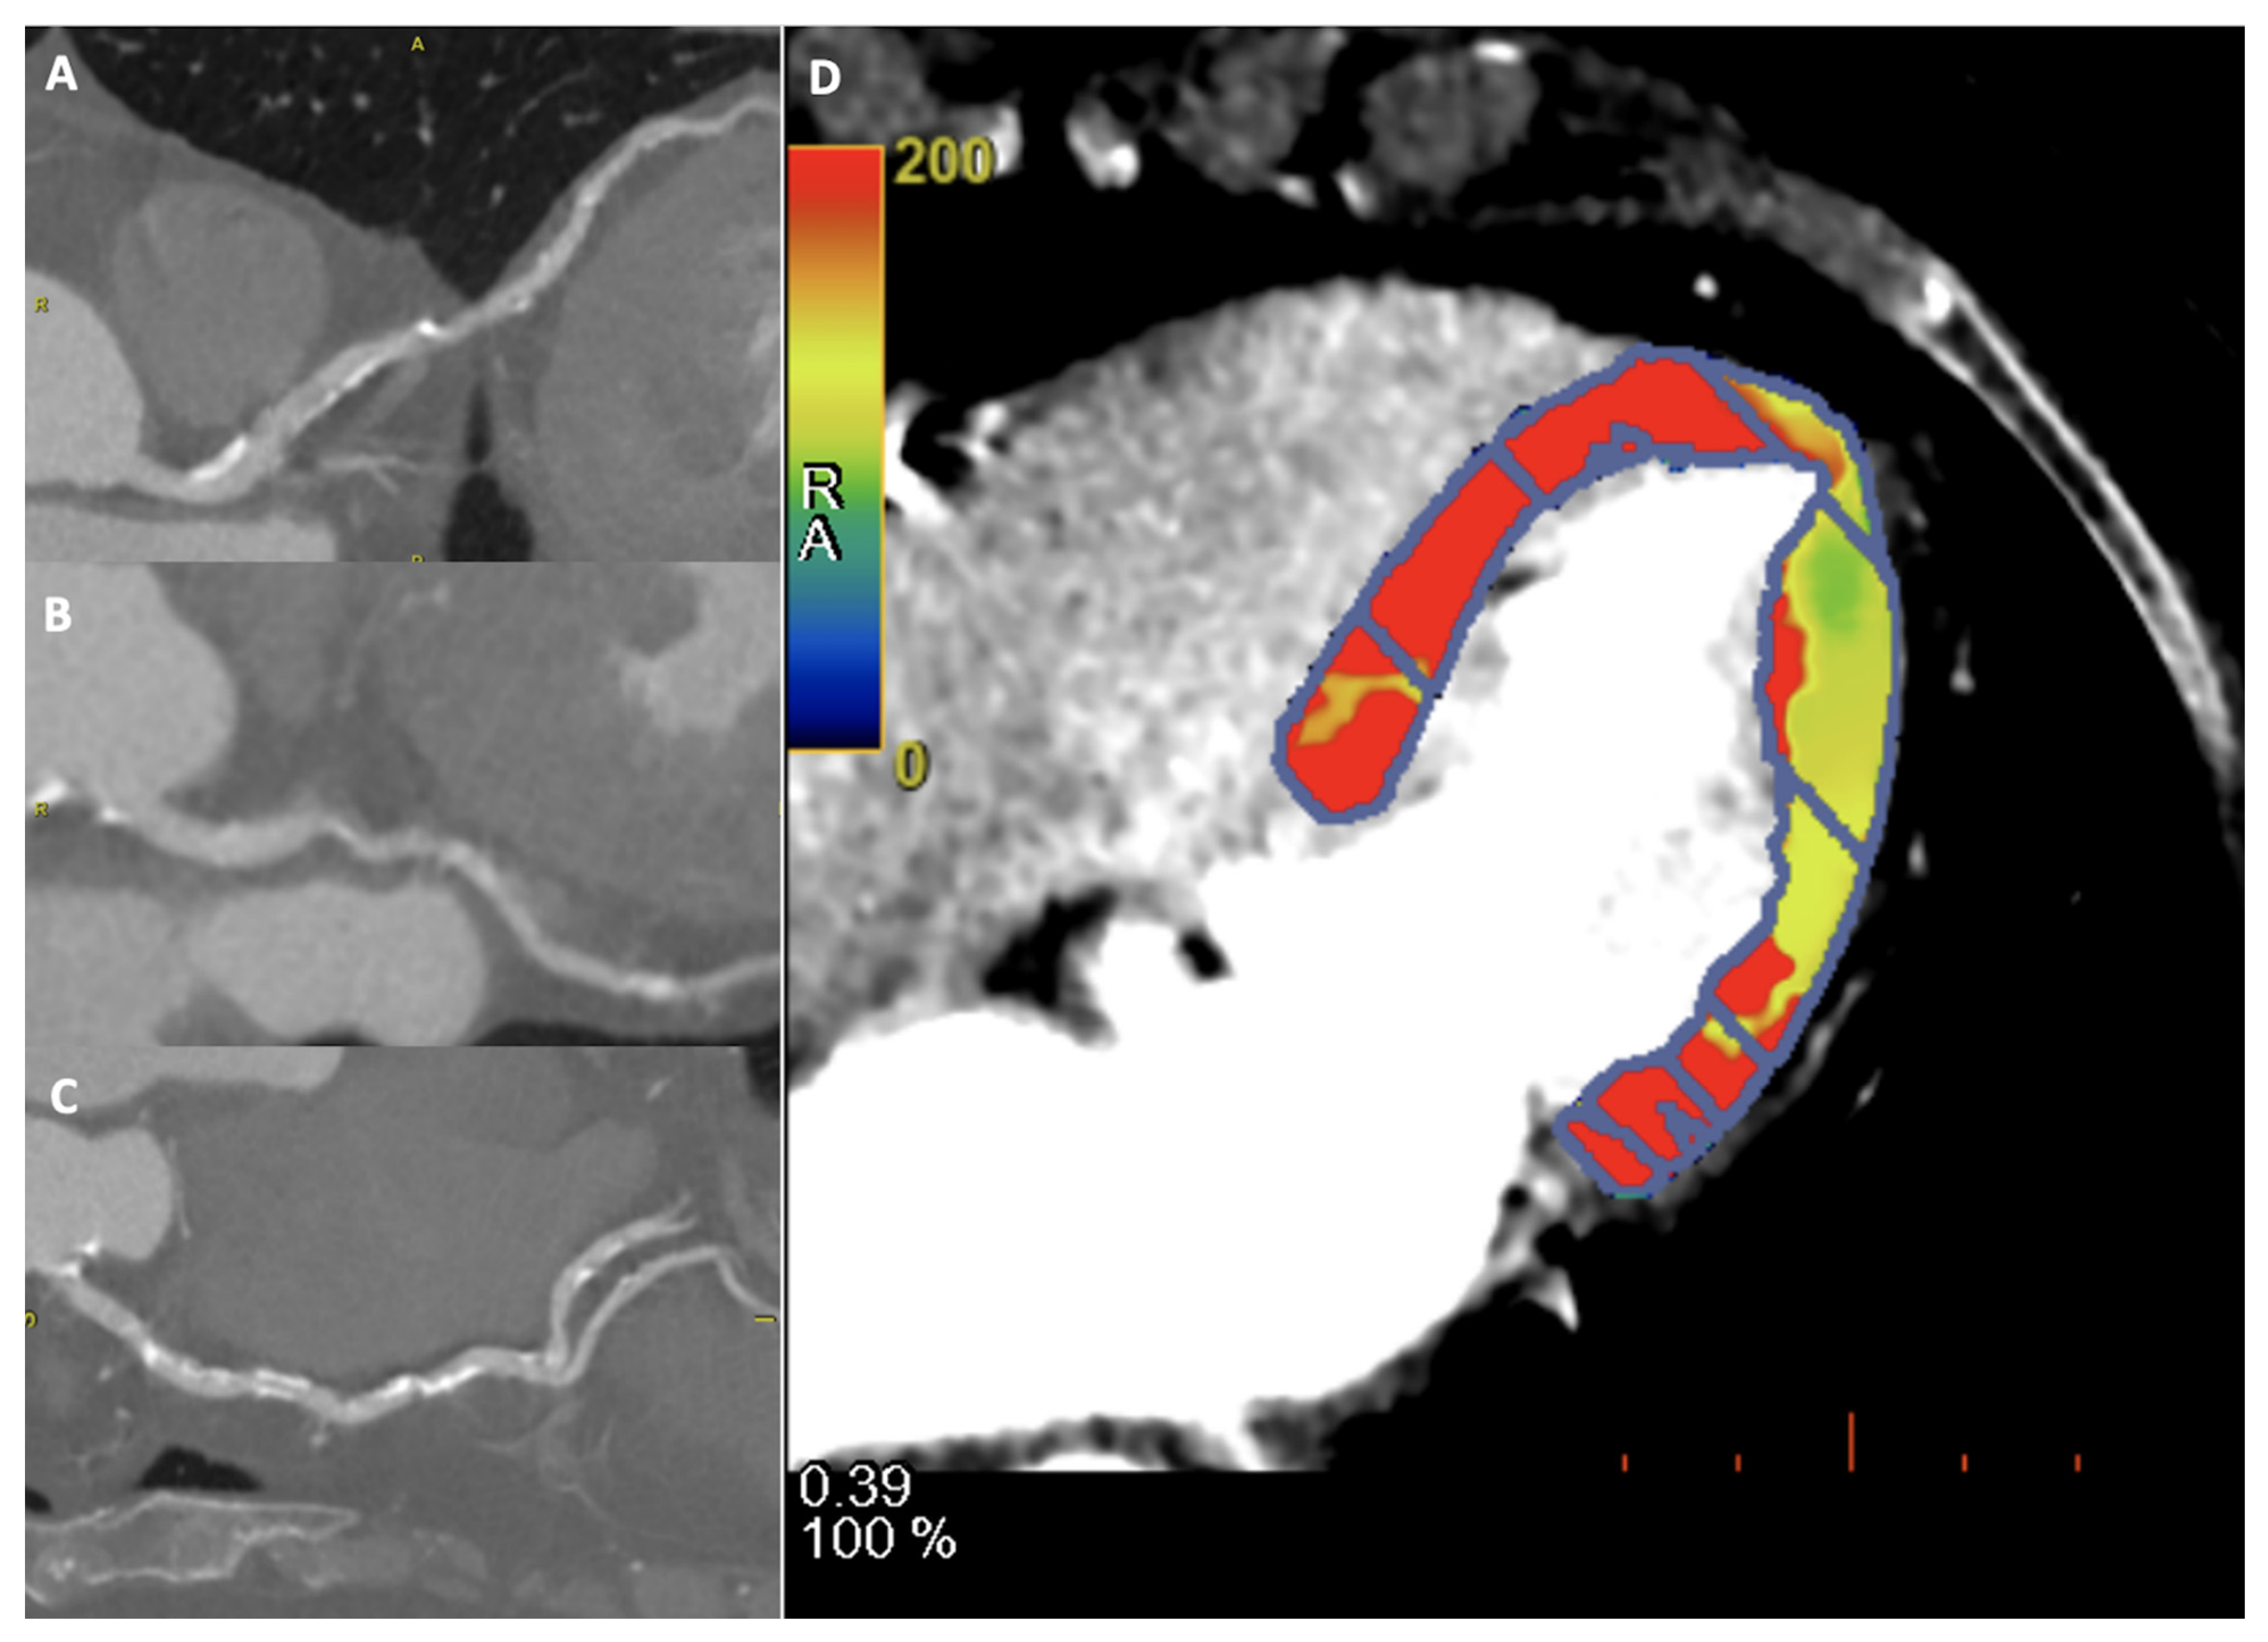

2.2. FFRct and CTP